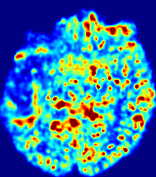

Slice #1Slice #2Slice #3Slice #4Slice #5Slice #6Dgtsuperscript𝐷gtD^{\text{gt}}Refer to captionRefer to captionRefer to captionRefer to captionRefer to captionRefer to caption(a)Refer to captionRefer to captionRefer to captionRefer to captionRefer to captionRefer to caption(b)Refer to captionRefer to captionRefer to captionRefer to captionRefer to captionRefer to caption(c)Refer to captionRefer to captionRefer to captionRefer to captionRefer to captionRefer to caption(d)Refer to captionRefer to captionRefer to captionRefer to captionRefer to captionRefer to caption(e)Refer to captionRefer to captionRefer to captionRefer to captionRefer to captionRefer to caption(f)Refer to captionRefer to captionRefer to captionRefer to captionRefer to captionRefer to captionRefer to caption000.060.060.060.120.120.120.180.180.180.240.240.240.300.300.30(mm2/s)𝑚superscript𝑚2𝑠(mm^{2}/s)

Figure 13: PIANO effectiveness and robustness testing: diffusion imaging via diffusion. Top row shows Dgtsuperscript𝐷gtD^{\text{gt}} used for simulating the ground truth pure diffusion. (a)-(f) refer to the results for D𝐷D estimated from the ground truth pure diffusion image time-series where Rician noise at levels 0%, 2%, 4%, 6%, 8%, 10% was added respectively.

Similarly, starting from the same initial condition C0superscript𝐶0C^{0} as in the ‘Advection Imaging’ experiment for each patient, we simulate concentration time-series {Cti(Ω)|i=0, 1,, 40}conditional-setsuperscript𝐶subscript𝑡𝑖Ω𝑖0140\{C^{t_{i}}\in\mathbb{R}(\Omega)|i=0,\,1,\,\ldots,\,40\} via a diffusion PDE, where we define the ground truth diffusivity D:=Dgtassign𝐷superscript𝐷gtD:=D^{\text{gt}} via the ADC map of the ISLES 2017 training set (ADC values are scaled by 0.000010.000010.00001 to ensure numerical stability):

Note this is likely not a spatially representative ground-truth for perfusion imaging, as it measures different effects from diffusion imaging. However, we still use it as a quasi-realistic pattern of diffusivity in the brain. We also added 2%, 4%, 6%, 8%, 10% levels of Rician noise to obtain simulations of ‘Diffusion Imaging’. The estimated Destsuperscript𝐷estD^{\text{est}} given concentrations of all noise levels for one patient are shown in Fig. 13, PIANO estimation results for all patients are summarized in Fig. 11 (b). Again, PIANO demonstrates its capability to recover the underlying diffusion field. In Fig. 13, when the noise level is increasing, some noisy patterns indeed appear in the associated Destsuperscript𝐷estD^{\text{est}}. Note that the ground truth diffusivity applied in this simulation experiment is about ten times larger than the diffusivity estimated in reality (Fig. 3, Fig. 4).